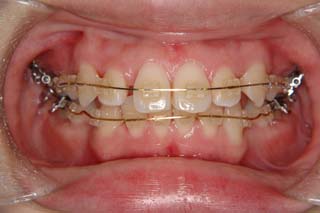

上顎前歯、下顎前歯の前突が見られます。大きな叢生は見られませんが、上下の口唇前突感も伴います。このような不正咬合を上下顎前突と言います。審美的な事もさることながら、歯軸の傾斜の問題から歯にかかるベクトルが良くない事、口唇の筋肉の緊張を強いるような不調和を示す事などから、不正咬合の一つとして考えられています。上顎前突傾向も伴っていますので、積極的に上顎前歯の後退を行う目的で、上顎に固定源となる 目的外使用の オーソアンカー SMAPシステム を装着しました。現在では、歯科矯正用アンカースクリュー(デュアルトップオートスクリュー、ISAアドバンスなど)といった、医療機器認証番号がある製品を用いることが多くなりました。

一般的なマルチブラケット装置を用いた治療では、先ずは形状記憶合金のワイヤーで大まかに配列を行い、バネをきかせたワイヤー、堅いワイヤーを使って仕上げていく方法です。